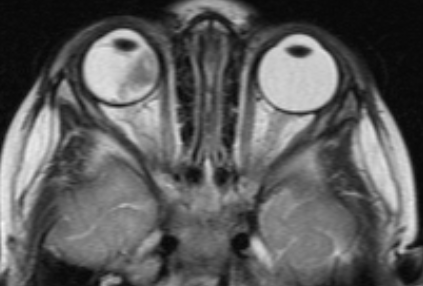

МРТ головного мозга и орбит

Магнитно-резонансная томография дает возможность в деталях увидеть распространение процесса за пределы глазного яблока и точно определить стадию болезни. Такое исследование нужно проводить всем пациентам, у которых ретинобластома диагностирована впервые. Контраст при МРТ повышает информативность.

![Визуализация ретинобластомы с помощью МРТ. Клиническая группа В]()

Рис. 2. Визуализация ретинобластомы с помощью МРТ. Клиническая группа В

![Визуализация ретинобластомы с помощью МРТ. Размеры образования соответствуют клинической группе D]()

Рис. 3. Визуализация ретинобластомы с помощью МРТ. Размеры образования соответствуют клинической группе D